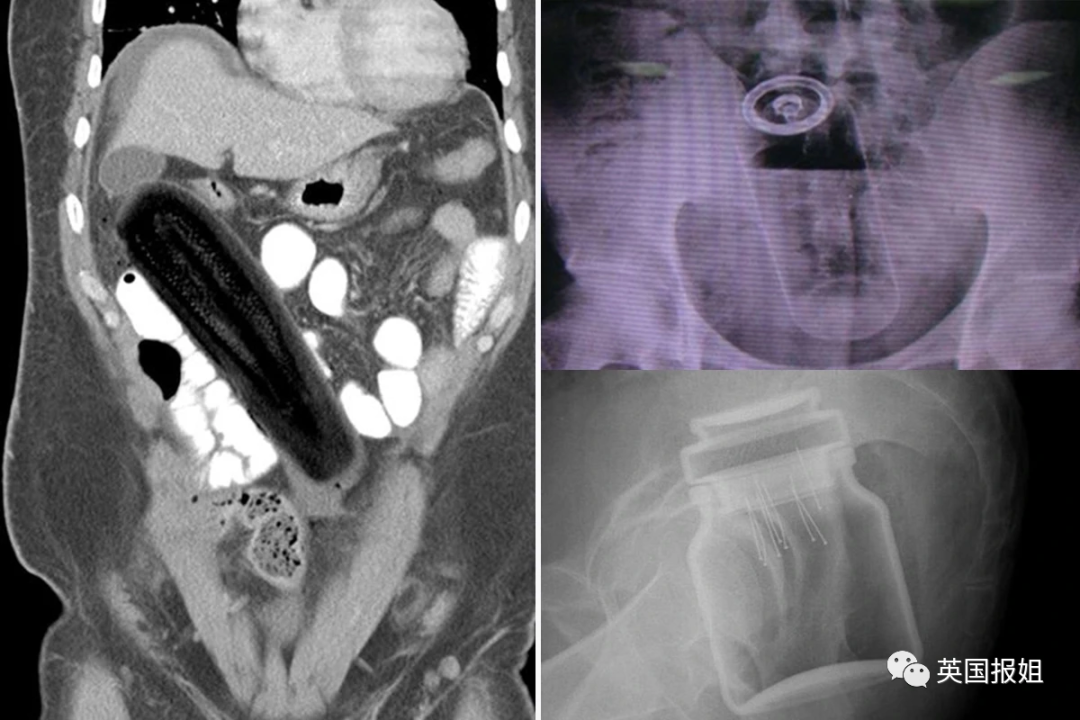

左:茄子 右上:铝罐 右下:咖啡罐

可以看出这些患者对于球形的、柱状的和长条形的物体有一些奇怪的执念。但有些患者也会突破这些形状的桎梏,寻找更多样的物品嵌入体内。

当固体已经满足不了他们的时候,还有人毅然决然选择了流体:这名美国27岁男子用胶枪将融化的黏合剂给自己灌肠,黏合剂进入体内后迅速凝固,坚若磐石:

图中的患者是一名72岁的老翁,他自称在上厕所时不慎跌倒在了一个倒着的酒瓶上: